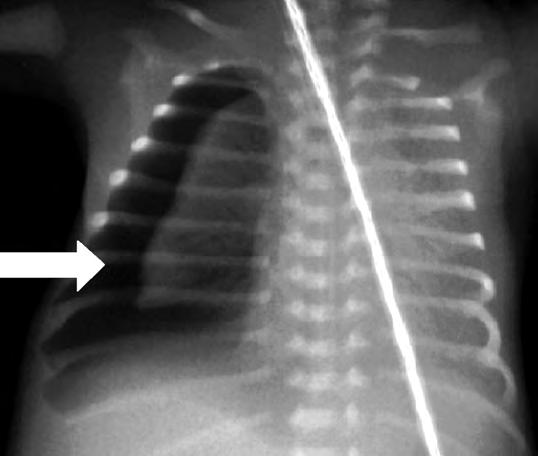

El patrón radiológico es muy variable y no guarda buena correlación con la gravedad clínica. Inicialmente se caracteriza por zonas infiltrativas con imágenes hiliofugales de intenso refuerzo junto con áreas de hiperinsuflación, y aire extraalveolar (Fig. 2.17.2). En las formas más graves suele predominar la imagen de atelectasia, edema y bajo volumen pulmonar probablemente por la inactivación del surfactante y fallo cardiaco relacionado con el episodio asfíctico concomitante.